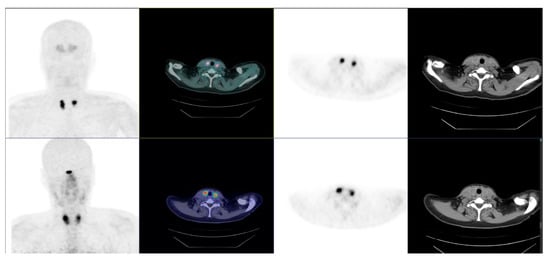

7.3. Molecular Imaging and Theragnostics

- Giovanella, L.; Treglia, G.; Iakovou, I.; Mihailovic, J.; Verburg, F.A.; Luster, M. EANM practice guideline for PET/CT imaging in medullary thyroid carcinoma. Eur. J. Nucl. Med. Mol. Imaging 2020, 47, 61–77. [Google Scholar] [CrossRef]

- Rasul, S.; Hartenbach, S.; Rebhan, K.; Göllner, A.; Karanikas, G.; Mayerhoefer, M.; Mazal, P.; Hacker, M.; Hartenbach, M. [18F]DOPA PET/ceCT in diagnosis and staging of primary medullary thyroid carcinoma prior to surgery. Eur. J. Nucl. Med. Mol. Imaging 2018, 45, 2159–2169. [Google Scholar] [CrossRef] [Green Version]

- Terroir, M.; Caramella, C.; Borget, I.; Bidault, S.; Dromain, C.; El Farsaoui, K.; Deandreis, D.; Grimaldi, S.; Lumbroso, J.; Berdelou, A.; et al. F-18-dopa positron emission tomography/computed tomography is more sensitive than whole-body magnetic resonance imaging for the localization of persistent/recurrent disease of medullary thyroid cancer patients. Thyroid 2019, 29, 1457–1464. [Google Scholar] [CrossRef]

- Asa, S.; Sonmezoglu, K.; Uslu-Besli, L.; Sahin, O.E.; Karayel, E.; Pehlivanoglu, H.; Sager, S.; Kabasakal, L.; Ocak, M.; Sayman, H.B. Evaluation of F-18 DOPA PET/CT in the detection of recurrent or metastatic medullary thyroid carcinoma: Comparison with GA-68 DOTA-TATE PET/CT. Ann. Nucl. Med. 2021, 35, 900–915. [Google Scholar] [CrossRef] [PubMed]